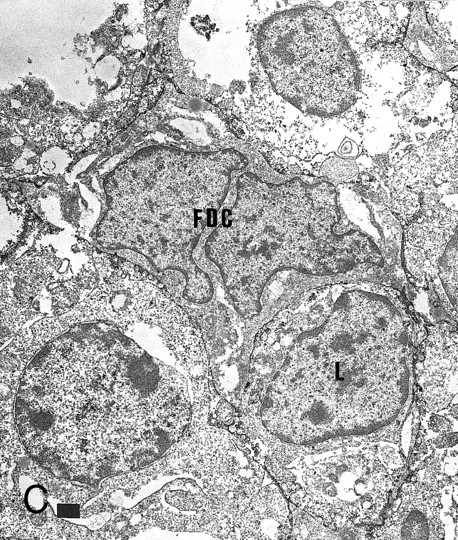

Expression of GM-CSF and GM-CSFRα in tonsillar lymphoid follicle. (A) Immunostain of GM-CSF. Some positive lymphocytes are scattered in the germinal center, but the distinct reticular pattern was not found. Counterstained with methyl green. Original magnification × 90. (B) Immunostain of GM-CSFRα. The distinct lacy pattern is found in the light zone and often in the outer and mantle zones. MZ, mantle zone; ALZ, apical light zone. Counterstained with methyl green. Original magnification × 240. (C) Immunoelectron micrograph of GM-CSFRα on FDC. Note a positive reaction on the surface of binucleated FDC embracing lymphocyte (L) of FDC. Bar = 1 nm. Original magnification × 5,700. (D) In situ hybridization of GM-CSFRα oligonucleotide. Dendritic-shaped cells are heavily labeled. Uncounterstained. Original magnification × 386.

Some GC lymphocytes were positive for GM-CSF (Fig 3A). No distinct positive reticular pattern was found in GC. On the other hand, the ALZ was heavily labeled in the reticular pattern and rarely in the dotted pattern for GM-CSFRα (Fig 3B). The BLZ was also weakly positive, and the OZ and MZ were often reacted. Immunoelectron microscopy confirmed that FDCs were positive for GM-CSFRα on their surface (Fig 3C). In situ hybridization also showed the expression of mRNA of GM-CSFRα in the cytoplasm of dendritic-shaped cells in the LZ and often in the OZ and MZ (Table 5 and Fig 3D). A few of the lymphocytes were positive for GM-CSFRα in the LZ. RT-PCR of samples from complete tonsillar tissue as well as GC and EGC showed a single-positive band (682 bp; Table 6 and Fig 2B).